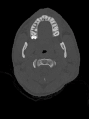

الأشعة المقطعية (بالإنجليزية: CT scan) أو التصوير الطبقي المحوري أو المِفْرَاس[1] هو أحد وسائل التصوير الطبي تعتمد على الأشعة السينية (أشعة إكس) تستخدم في تكوين صورة ثلاثية الأبعاد لأعضاء الجسم الداخلية. وتتكون عن طريق عدة صور ثنائية الأبعاد تُلتقط حول محور ثابت للدوران.

يتميز التصوير المقطعي المحوسب بوضوح عالي جدًا للصورة ويُظهِر تفاصيل العظام بشكل متناهي الدقة بعكس تصوير الرنين المغناطيسي الذي يصور الأنسجة الرخوة بدقة عالية، وَهذا الإجراء خالٍ من الألم.

تُعالج المعلومات والصور الناتجة عن جهاز التصوير المقطعي لتظهر أعضاء الجسم حسب قدرتها على منع مرور الأشعة السينية عبرها، وأيضا يمكن أن تستخدم هذه المعلومات في رسم صور ثلاثية الأبعاد، وَالصور التي يتم الحصول عليها هي مَقْطَعِيَّة عرضية بطبيعتها، وكل شريحة تَصْوير ثنائية الأبعاد تشبه مثلاً ما تراه عندما تقوم بقَطْع تفاحة إلى نصفين عبر الوسط ومن ثم تنظر إلى سطح القطع؛ فإذا بدأت ذلك من أعلى التفاحة نزولاً إلى الأسفل فسوف تحصل على سلسلة من الشرائح التي تمثل التركيب الكلي. وبالاستعانة بالحاسوب فإنه يمكن إعادة تركيب صور ثلاثية الأبعاد من هذه الشرائح الثنائية الأبعاد. استخدام هذا النوع من الأجهزة شائع جدا حول العالم، فمثلا في الولايات المتحدة 80 مليون شخص يخضعون لهذا التصوير سنوياٌ، و50 مليون في اليابان.[2] يخشى العلماء أن استخدام هذا النوع من التصوير بشكل زائد قد يؤدي إلى سرطانات. ليس الأطباء وحدهم من يستخدمون هذا الجهاز، فعلماء الآثار أيضا يستخدمونه في فحص الآثار القديمة كالتوابيت.[3]